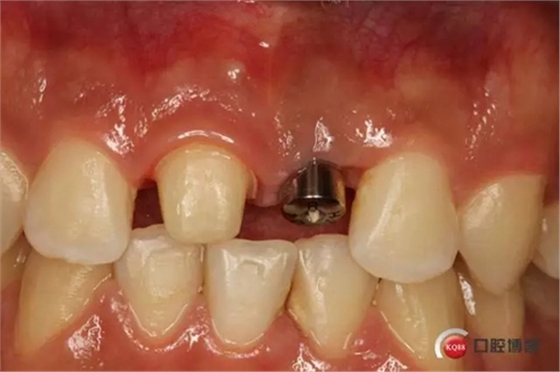

種植后修復(fù),我們要把握每一個(gè)細(xì)節(jié),比色,轉(zhuǎn)移桿的就位,我們必須把臨床做好,技工師傅才會(huì)給我們做出好的修復(fù)體,減少一些不必要的失誤,首先術(shù)前的檢查是必要一步 ,再是器械的準(zhǔn)備使我們臨床操作有條不紊,術(shù)前拍照,o-bite取咬合記錄,消毒修復(fù)術(shù)區(qū),旋出愈合基臺(tái),生理鹽水沖洗袖口,拍照袖口,安放合適轉(zhuǎn)移桿,拍X線見(jiàn)轉(zhuǎn)移桿就為良好,硅橡膠取模,術(shù)后旋回愈合基臺(tái),拍照比色。